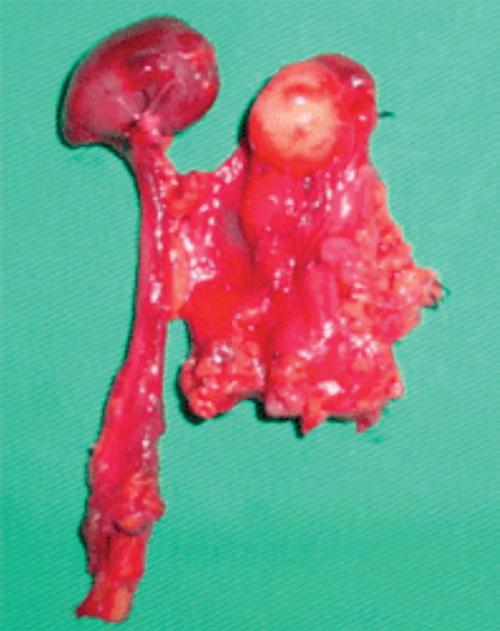

Percutaneous drainage of iliopsoas abscess: an effective option in cases not suitable for surgery

DOI: 10.1590/S1679-45082018RC4254

ABSTRACT The aim of this study were to describe the technique of percutaneous drainage of iliopsoas abscess, and to discuss the benefits of using this minimally-invasive tool. A single center study with retrospective analysis of patients with psoas abscess confirmed by imaging scans, sent to the interventional medicine center and submitted to computed tomography and ultrasound-guided percutaneous drainage, from November 2013 to August 2016. Seven patients underwent percutaneous drainage of psoas abscess in this period. The mean initial drained volume […]

Keywords: Drainage; Minimally invasive procedures; Psoas abscess/diagnostic imaging; Tomography, x-ray computed; Ultrasonography